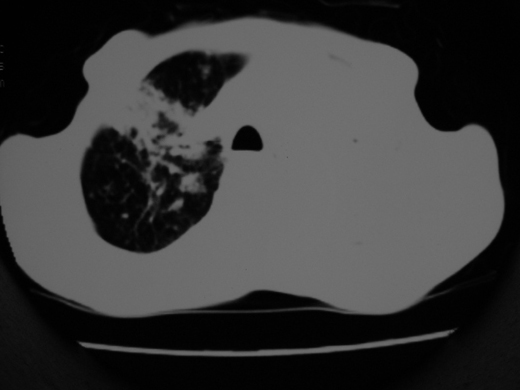

双肺内不规则斑点状 片状及结节密实影,部分灶周见索条样影及\"树芽征\",左肺上叶实变,内见充气支气管影及斑状钙化,左侧少量胸腔积液,考虑1)双肺结核2)左侧胸腔积液

右肺多发片絮状结节状及时条索状影,左上肺实变,内可见虫蚀样空洞及支气管气象,左下肺片状及球形病灶,及胸腔积液征象,双肺病灶内多发钙化影,结合病史,考虑双肺继发型肺结核,左胸腔积液

右肺多发片絮状结节状及时条索状影,左上肺实变,内可见虫蚀样空洞及支气管气象,左下肺片状及球形病灶,及胸腔积液征象,双肺病灶内多发钙化影,上纵隔向左侧移位,结合病史,考虑双肺继发型肺结核,左胸腔积液。

右肺多发片絮状、结节状及条索状影,左上肺实变,内可见虫蚀样空洞及支气管气象,左下肺片状及球形病灶,有胸腔积液征象,双肺病灶内多发钙化影,上纵隔向左侧移位,结合病史,考虑双肺继发型肺结核,左胸腔积液。 建议结合ppd检查或纤支镜检查!

右肺可见大片状、云絮状改变。右肺可见散在类圆形影,以外带多见。左肺实变,其内可见明显支气管走行影。纵隔淋巴结有增大,左侧胸腔积液。考虑1、肺结核;2、肺癌肺转移不除外;3、左侧胸腔积液。